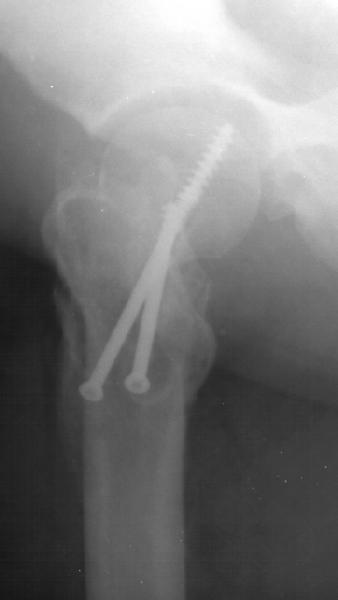

The valgus osteotomy has improved the position of the femoral neck fracture

The blade plate is in the anterior and proximal aspect of the femoral head

What activity level is planned? Keep a close eye on the femoral head and neck. They will determine outcome, primarily.